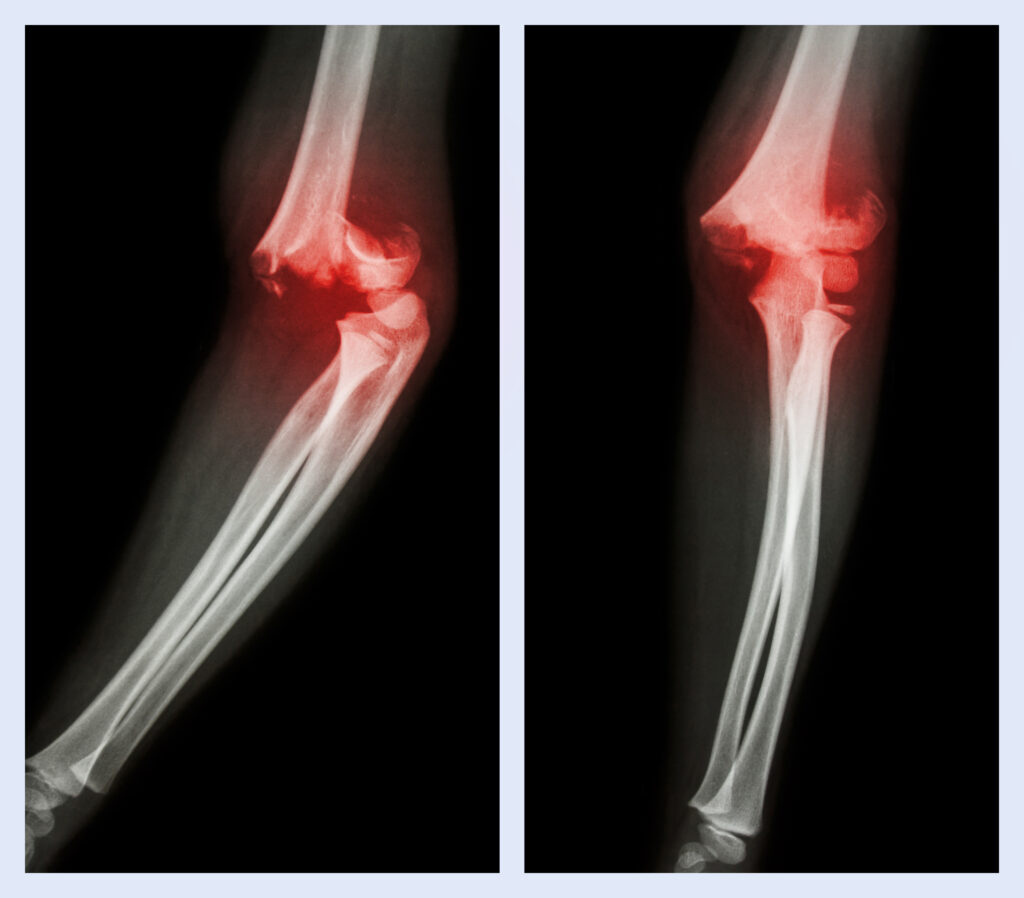

An elbow dislocation occurs when the bones of the forearm (radius and ulna) move out of their normal position in relation to the upper arm bone (humerus). It is one of the most common types of joint dislocations after the shoulder and can range from simple (without bone fracture) to complex (with associated fractures or ligament damage).

Types of Elbow Dislocations1.Simple Dislocation – bones are displaced but there are no fractures.

2.Complex Dislocation – bones are displaced along with fractures around the elbow joint.

3.Partial (Subluxation) – bones are partially out of alignment but not fully dislocated.

4.Complete Dislocation – bones are completely out of their normal position.

Visible deformity or abnormal positioning of the elbow